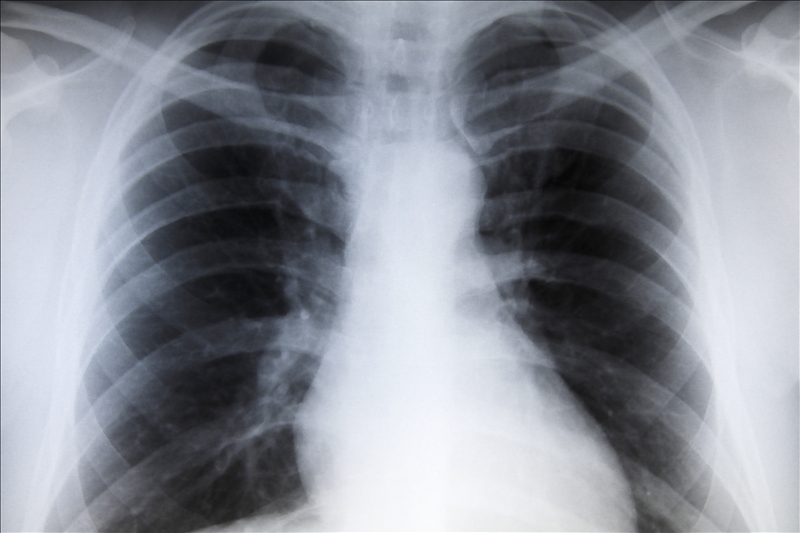

• Right Heart Failure---This occurs when the right side of the heart is unable to sufficiently pump venous blood into the pulmonary circulation. The lungs may not receive enough blood. All of this results in a back-up of fluid in the body, producing edema and congestion that may affect the liver, the gastrointestinal tract, and the limbs.

• Left Heart Failure---The left side of the heart gets blood directly from the lungs, where it has been oxygenated. If it is unable to adequately pump that blood into the rest of the body, then the rest of the body does not have enough oxygen, resulting in fatigue, shortness of breath, and pulmonary edema.